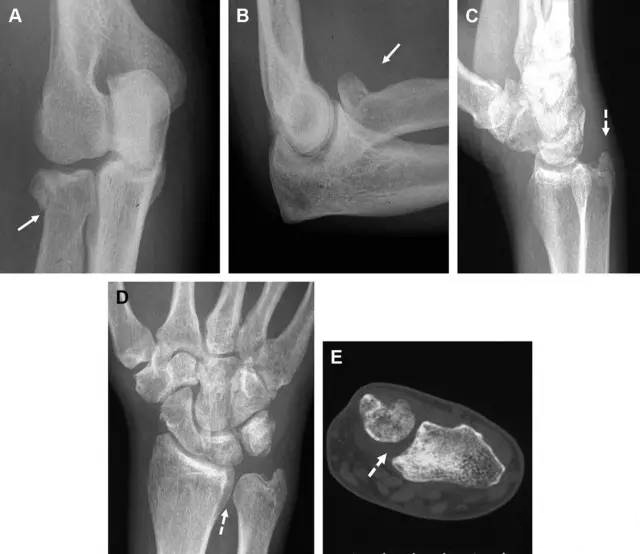

Essex-Lopresti 损伤是桡骨头骨折伴有下尺桡关节脱位,导致骨间膜损伤,桡骨短缩。此种损伤,桡骨头骨折的诊断往往是明确的,容易忽视的是下尺桡关节脱位,特别是早期,下尺桡关节的症状不明显,X 线表示也不明显。

图8 Essex-Lopresti 损伤。前后位(A)和侧位(B)示桡骨头关节内骨折(白色实线箭头);(C~E)伤后 1 个月复诊,患者诉腕关节疼痛,X 线(C,D)发现下尺桡关节脱位,(E)CT 进一步证实损伤的存在